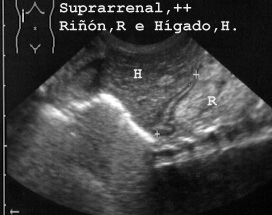

En la Fig 47 se ve la suprarrenal en sección longitudinal.

Pero así como en los niños las suprarrenales son muy fáciles de observar, en los adultos sólo las vemos cuando están aumentadas de tamaño como ocurría en la Fig 48 debido a infiltración por un linfoma.